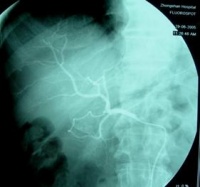

可进行必要的检查化验。若血常规显示小细胞性贫血,血沉增快,大便潜血试验持续阳性;X线表现为钡剂充盈缺损,病变肠壁僵硬,蠕动减弱或消失,结肠袋不规则,肠管狭窄或扩张等,即可确定为已患上第五日综合征。